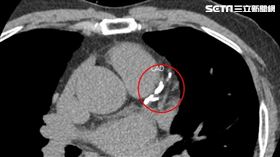

55歲男菸酒不拒 健檢心臟這裡塞住

陳老闆最近常胸悶、頭暈、呼吸急促,趁著疫情趨緩安排健...